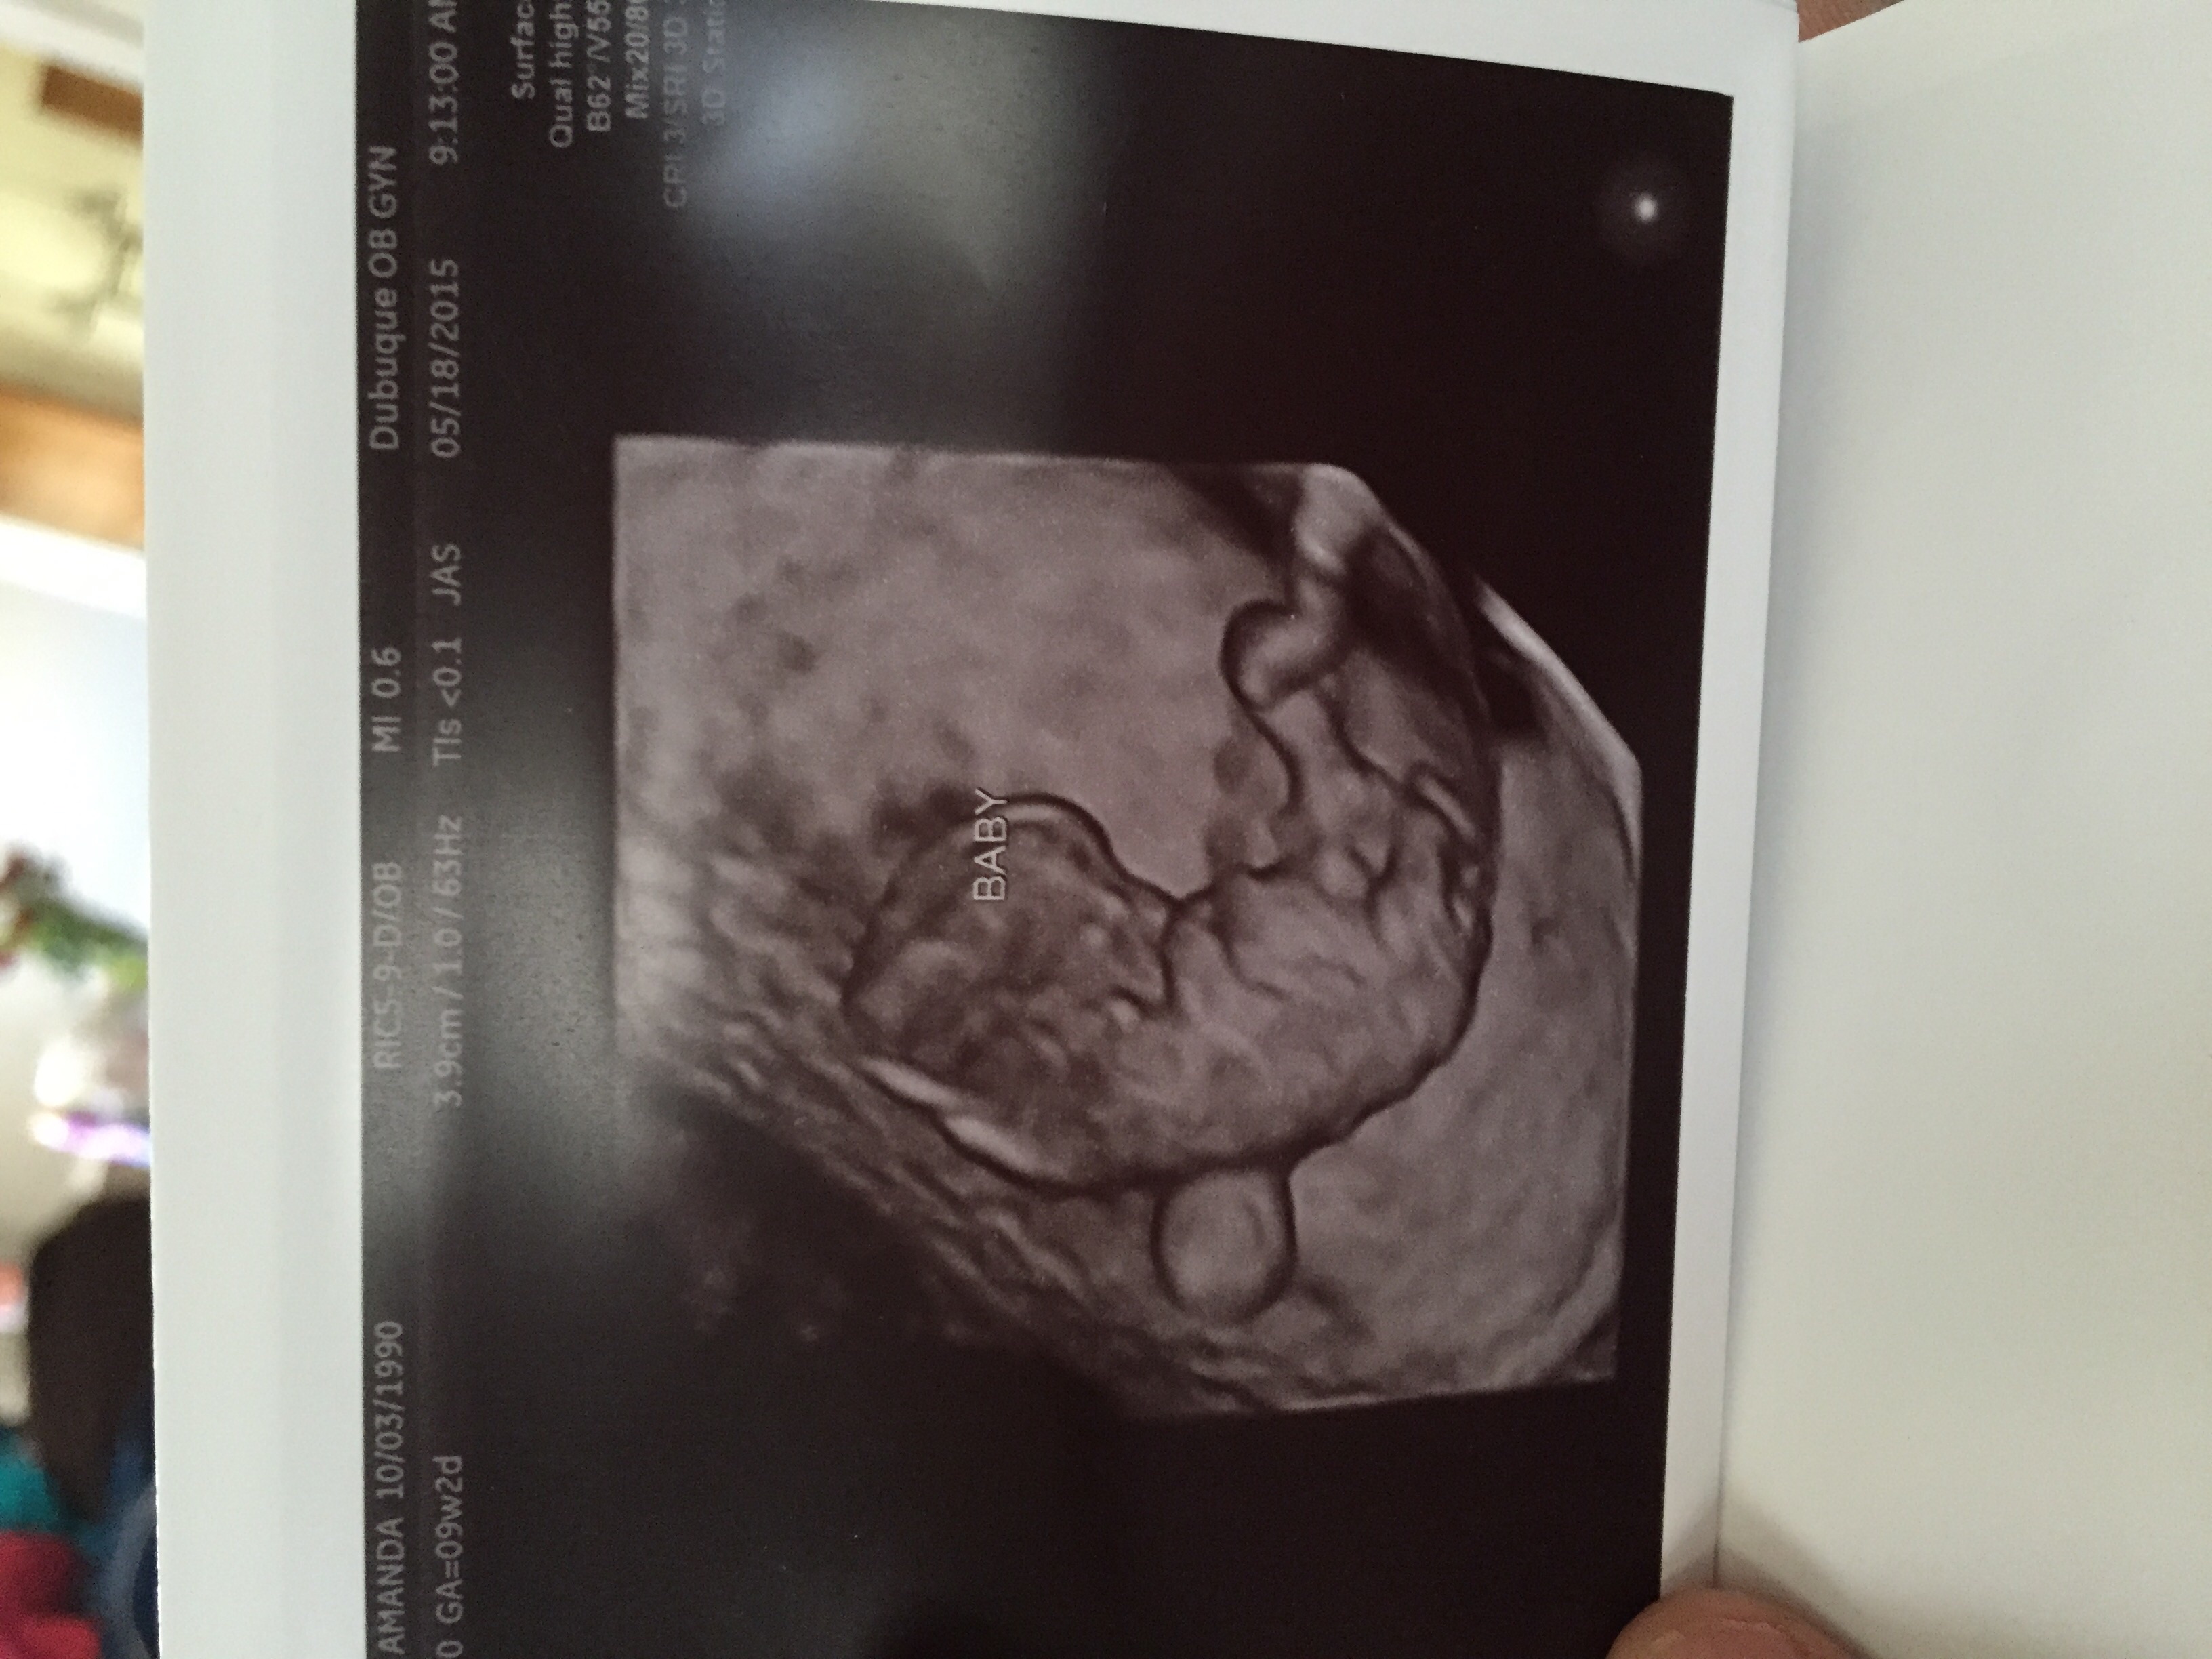

Taken at 8w6d but measuring 8w3d for now. We saw the heart flickering and the baby was waiving arms!! Cute Cute Cute, so happy! I go back in 3 weeks for another one.